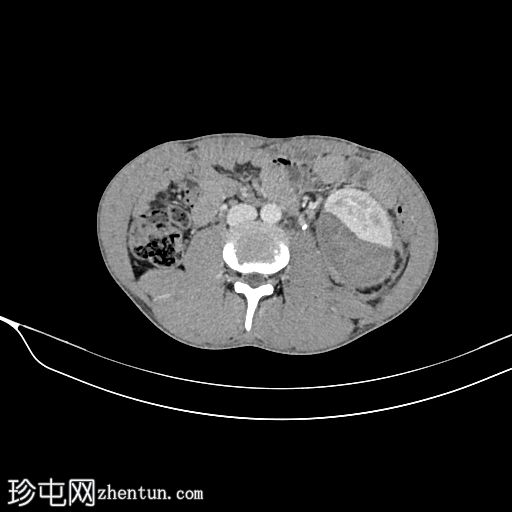

轴位

平扫

左肾包膜下(毗邻肾后包膜)可见一相对高密度、无强化的积液(平扫时HU=70),包绕左肾。

左肾下极可见肾实质不连续(>1 cm,未累及集合系统),提示

肾脏

撕裂伤部位。

左肾受巨大血肿压迫;但可见肾实质强化正常,造影剂排泄至集合系统。未见造影剂外渗。

III级肾损伤的特征(撕裂伤>1厘米,未累及集合系统,血肿局限于肾周筋膜内)